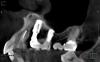

syrovovec Опубликовано 27 августа, 2013 Поделиться Опубликовано 27 августа, 2013 Коллеги!помогите советом. Планируется удаление корня,имплантов,засыпаться,подождать,закрутить. Засыпать Bio-oss. Вопрос в том,потребуется в дальнейшем синус? Ссылка на комментарий

bullbull Опубликовано 27 августа, 2013 Поделиться Опубликовано 27 августа, 2013 А как долго простояли винты до того, как обрели свободу движения? Что за фирма?Синус открытый, но сразу я бы не делал. Ссылка на комментарий

syrovovec Опубликовано 29 августа, 2013 Автор Поделиться Опубликовано 29 августа, 2013 (изменено) А как долго простояли винты до того, как обрели свободу движения? Что за фирма?Синус открытый, но сразу я бы не делал.Радиксы.2 года,дистальный установлен со 2 раза.как-то сложно протекал п/о период.Я так понял что они всегда были подвижны Изменено 29 августа, 2013 пользователем syrovovec Ссылка на комментарий